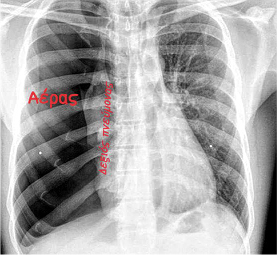

ΠΡΩΤΟΠΑΘΗΣ  ΑΥΤΟΜΑΤΟΣ  ΠΝΕΥΜΟΘΩΡΑΚΑΣ Η παρουσία αέρα στην υπεζωκοτική κοιλότητα σημαίνει τρία πράγματα: α).  Συνεπεία τραυματισμού και είσοδος ατμοσφαιρικού αέρα. β).